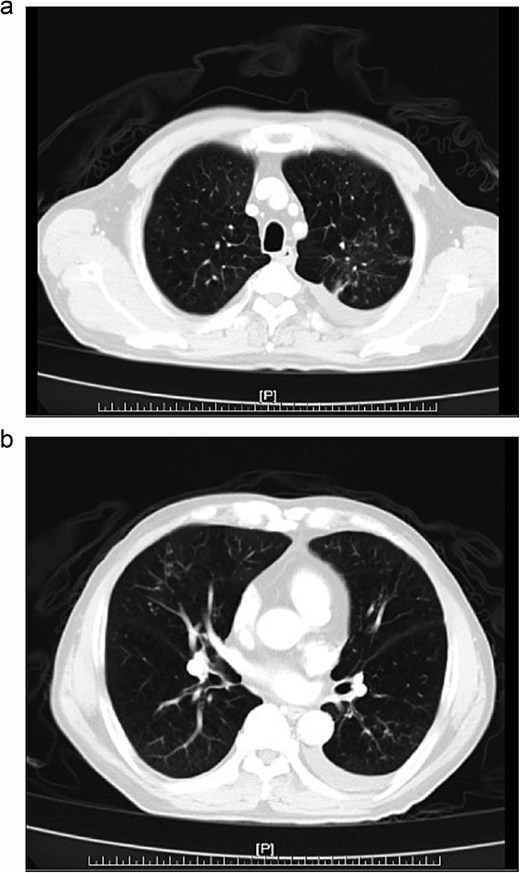

Further diagnostic evaluation with computed tomography (CT) of the abdomen and lungs was conducted. The abdominal CT revealed mild peritoneal thickening with multiple miliary nodules and omental cake with ascites (Fig. 1a and b), while the lung CT demonstrated multifocal of patches of centrilobular nodules and tree-in-bud in bilateral lungs (Fig. 2a, b).

(a, b) Chest CT, multifocal of patches of centrilobular nodules and tree-in-bud in bilateral lungs.